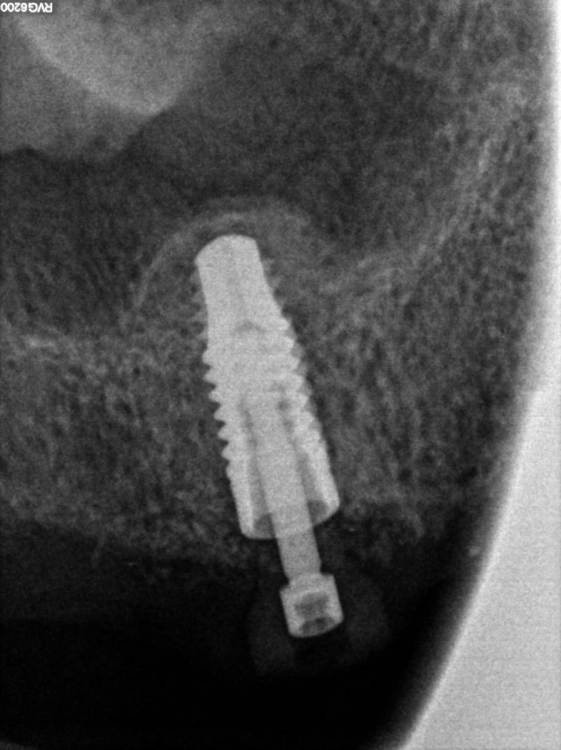

TIGER Опубликовано 11 августа, 2022 Поделиться Опубликовано 11 августа, 2022 Всем ? привет!закрытый синус через нави (шаблоны изготавливаю сам)и под контролем скопа,посадка на 12 часов всегда.и важно имплант с неагрессивным апексом ,преп ложа- проламывание дна фрезами DENSAH на реверсе 9 1 Ссылка на комментарий

TIGER Опубликовано 6 декабря, 2022 Автор Поделиться Опубликовано 6 декабря, 2022 Сегодня на осмотре и замере КСИ,всё отлично,отправил на протезирование 2 1 Ссылка на комментарий

TIGER Опубликовано 7 декабря, 2022 Автор Поделиться Опубликовано 7 декабря, 2022 @АнтонТЛТ @Irouil Друзья ПЕРИОтест от слова ПЕРИОдонт?у импланта нет его,и замерять им не совсем корректно,у импланта совсем другие принципы @Korabahtoff спасибо !тут TITAMAX 4.0 Ссылка на комментарий

TIGER Опубликовано 9 марта, 2023 Автор Поделиться Опубликовано 9 марта, 2023 прошло 6 мес,кт 6 Ссылка на комментарий